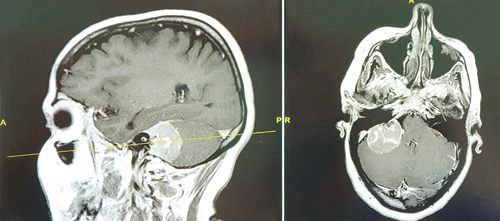

وقال د. المسعود إن الفريق الطبي تعامل مع الحالة بشكل سريع؛ إذ تم إجراء الفحوصات الدقيقة اللازمة، وأُخذت لها صورة رنين معناطيسي، وأظهرت النتائج إصابتها بورم كبير في قاع الدماغ بين المخيخ وعنق الدماغ من الجهة اليمنى مسببًا ضغطًا شديدًا على مراكز الحركة والأعصاب والسمع. وبعد دراسة مستفيضة ومتكاملة للحالة على ضوء نتائج الفحوصات الطبية قرر الفريق الطبي إجراء عملية عاجلة في وضعية الجلوس، استمرت «8» ساعات، تم فيها استئصال كامل الورم بدقة متناهية - بفضل الله - مع المحافظة على شرايين وأعصاب الدماغ المحيطة. وما يجدر ذكره هو أن وضعية الجلوس تمثل أسلوبًا علاجيًّا آمنًا؛ إذ تقلل من احتمالات تعرُّض بعض مناطق الدماغ الحساسة للتلف، وتُستخدم عادة في علاج بعض الحالات الدماغية، مثل أورام الدماغ ونوبات الصرع. وأضاف: بعد «24» ساعة من العملية أظهرت المؤشرات والعلامات الحيوية تحسُّن الوضع الصحي للمريضة، وتأكد ذلك من خلال إجراء صور الأشعة المقطعية والرنين المغناطيسي. ولاحقًا تم تحويل المريضة إلى قسم التنويم العام، واستمرت حالتها في التحسن باطراد مع العناية الطبية الحثيثة لمدة «10» أيام، ثم غادرت المستشفى بعد أن أكدت الفحوصات السريرية الدورية الدقيقة شفاءها التام من الأعراض كافة التي كانت تشكو منها. ونبه د. المسعود إلى أن أورام الدماغ تعد من أعقد الأمراض لحساسية موقعها، وشدة المضاعفات الصحية المترتبة عليها.. وحذر من أن إهمالها قد يؤثر بشكل جذري على حياة المريض. مشيرًا إلى أن من يشعرون بأعراض أورام الدماغ، كازدواج أو عدم وضوح الرؤية، والفقدان التدريجي للإحساس والتوازن، وعدم القدرة على التركيز، يتعيّن عليهم زيارة الطبيب بشكل فوري. الجدير بالذكر أن مستشفيات مجموعة د. سليمان الحبيب الطبية تمتلك الإمكانات كافة التي تساعدها على تقديم أفضل رعاية متكاملة لمرضى جراحات المخ والأعصاب من خلال جراحين على مستوى عالٍ من التأهيل والخبرة، وأقسام طوارئ تعمل على مدار الساعة لاستقبال حالات الجلطات الدماغية ومشكلات المخ والأعصاب، إضافة إلى عيادات تشخيصية مجهزة، وكذلك وحدة عالية التجهيز للعناية المركزة ICU التي تقدم وسائل الرعاية كافة لهؤلاء المرضى، وأيضًا غرف العمليات المجهزة على أعلى مستوى لتلك الإجراءات الجراحية الدقيقة.